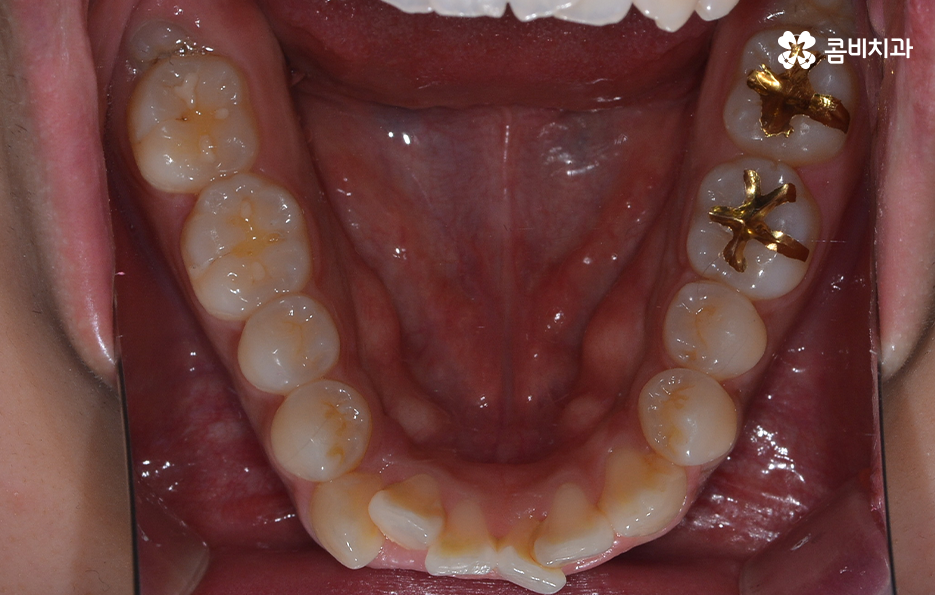

치아교정을 위한 발치교정 과정은 대부분 소구치 라고 불리는 첫번째 작은 어금니를 발치하게 되며 좌우, 위 아래 총 4개의 소구치를 발치한 후에 덧니가 재배열 될 수 있는 공간을 만들기 위하여 우선 송곳니를 후방으로 이동시키고 있어요

그 다음으로는 송곳니가 후방으로 이동하면서 확보된 공간으로 앞니의 배열을 가지런하게 맞추고 있는데요. 앞니의 재배열과 함께 발치 교정으로 인해 빈 공간이 발생한 부분을 없애고 전체적인 치열을 미세하게 조절하게 되는데 발치교정은 치아의 움직임이 많은 편이기 때문에 교합이 잘 맞도록 마무리 배열을 잘해야 하며 그와 함께 치아가 많이 움직이는 만큼 얼굴형의 변화와 입술라인 등의 변화가 클 수 있다는 점에서 치료 후 결과를 잘 예측하여 처음 치료 계획부터 마무리까지 섬세하게 진행하실 필요가 있어요